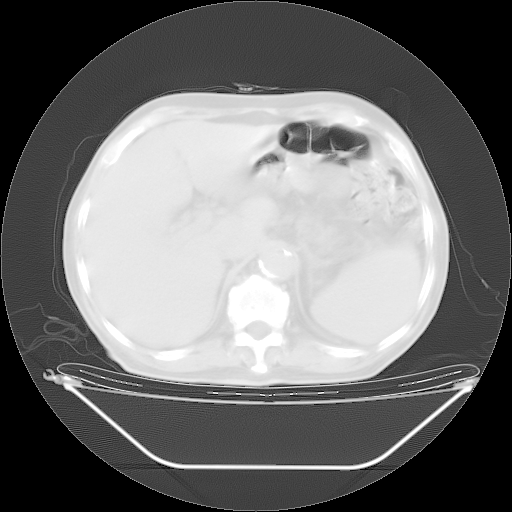

5月9日肺部CT(在4月27日齐鲁医院肺部CT描述部分肺组织磨玻璃样改变,12天后肺组织广泛磨玻璃样改变)

2009年5月9日肺部CT

大致读了系列胸部CT:纵隔窗无明显异常,肺窗:从4、27至今:主要是双肺中下野外带可见毛玻璃样改变,目前处于急性肺泡炎阶段,至于原因考虑1、结替组织或胶原血管性疾病所致?2、恶性疾病如恶组在肺部所致的表现或细支气管肺泡癌?3、药物或其它原因如肺蛋白沉着症所致肺泡炎目前不太可能?总之,明天就去请我院的呼吸科、感染科、血液科和临免专家会诊哈。